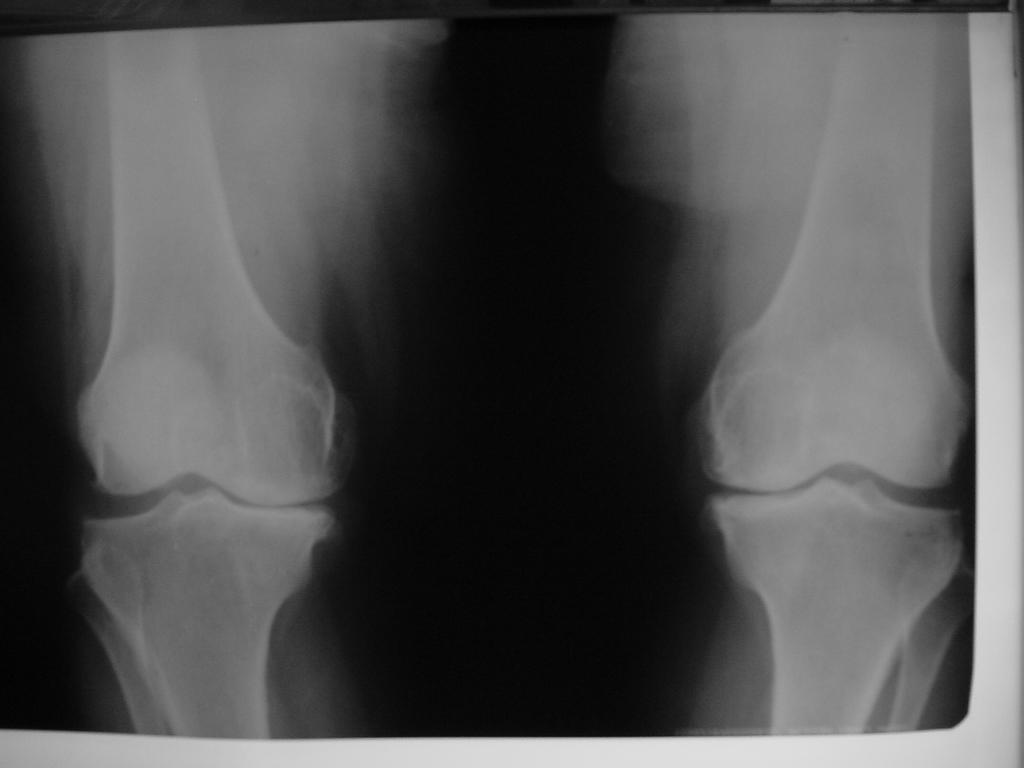

Total Diz Protez ameliyatı kliniğimizde endikasyon dahiline her yaşa başarı ile uygulanmaktadır. Örnek olgumuz: